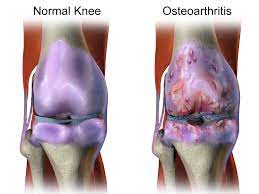

급성 감염성 관절염

보통 증상은 몇 시간에서 며칠에 걸쳐 시작됩니다. 감염된 관절은 보통 심한 통증을 수반하고 때때로 불그스름하고 따뜻합니다. 이를 움직이거나 만지면 매우 아픕니다. 감염된 관절에 액체가 축적되어, 부기와 뻣뻣함을 야기합니다. 때때로 열, 오한이 증상으로 나타납니다. 매우 드물게 패혈성 쇼크가 발생합니다.

임균성 관절염

보통 보다 경증의 증상들을 야기합니다. 일반적으로 5 ~ 7일 동안 열이 납니다. 피부 수포, 융기, 궤양 또는 발진이 나타나거나 구강 또는 생식기 및 몸통, 손 또는 다리에 궤양이 나타날 수 있습니다. 관절이 붓고 아프기 전, 통증이 한 관절에서 다른 관절로 옮겨갈 수 있습니다. 힘줄에 염증이 생길 수 있습니다.

만성 감염성 관절염

보통 점진적인 부기, 경증의 온감, 관절 부위의 미미한 발적 또는 발적 부재, 경증이고 급성 감염성 관절염보다 덜 중증일 수 있는 욱신욱신 쑤시는 통증입니다. 보통 단일 관절이 침범당합니다.